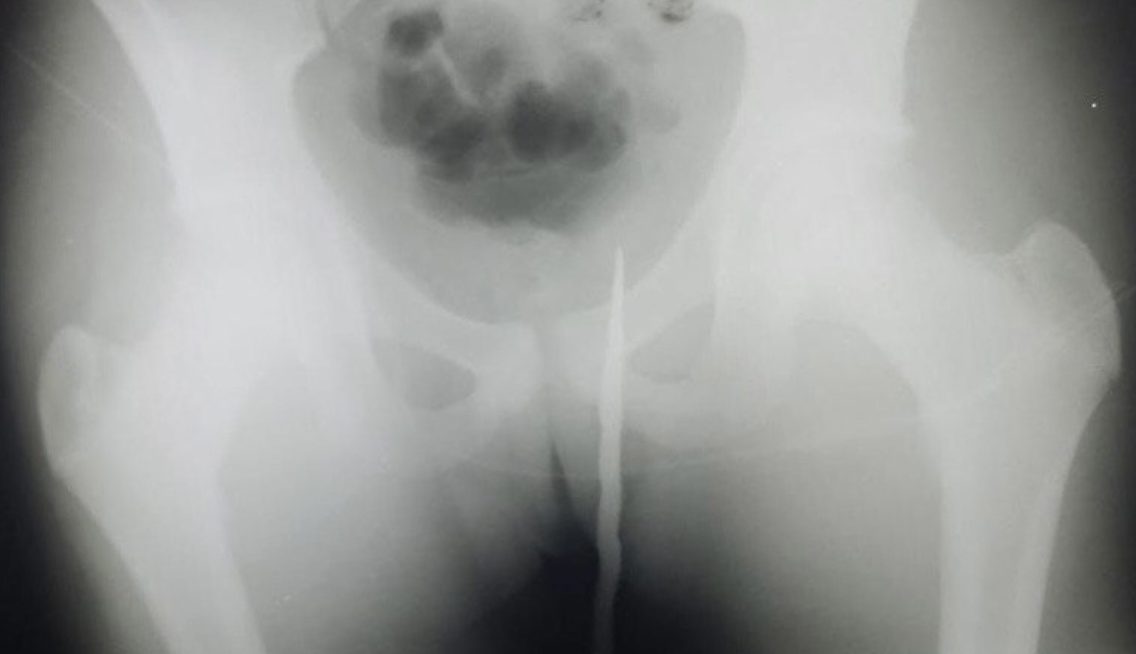

В подмосковном Наро-Фоминске 14-летний школьник гулял в лесу с друзьями и напоролся на штык от винтовки ягодицами. Об этом говорится на сайте министерства здравоохранения Московской области.

Сообщается, что постращавшего доставили больницу — в его ягодицы врезался ржавый штык от винтовки. По словам врачей, травма оказалась серьёзной, так как штык вонзился в мягкие ткани более, чем на 15 сантиметров. Был риск повреждения внутренних органов мальчика.

В результате было принято решение провести экстренную операцию. Отмечается, что хирургам удалось извлечь холодное оружие под общим наркозом. Всё прошло успешно — школьника выписали после непродолжительного послеоперационного периода.